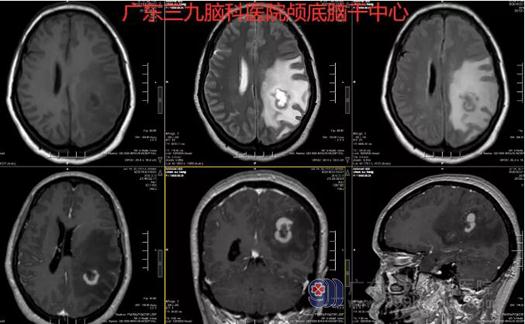

图2:术前MR示左侧顶叶示类环形病灶,T1WI呈外稍高内低异常信号,T2WI呈外偏等内高异常信号,FLAIR序列呈偏等-高-偏等异常信号,增强后类半环形强化,强化不均,周围示大片状水肿信号。左侧侧脑室受压。

图3:术前术后MR示左侧颞顶枕骨不连呈术后改变,左侧顶叶病变已切除。